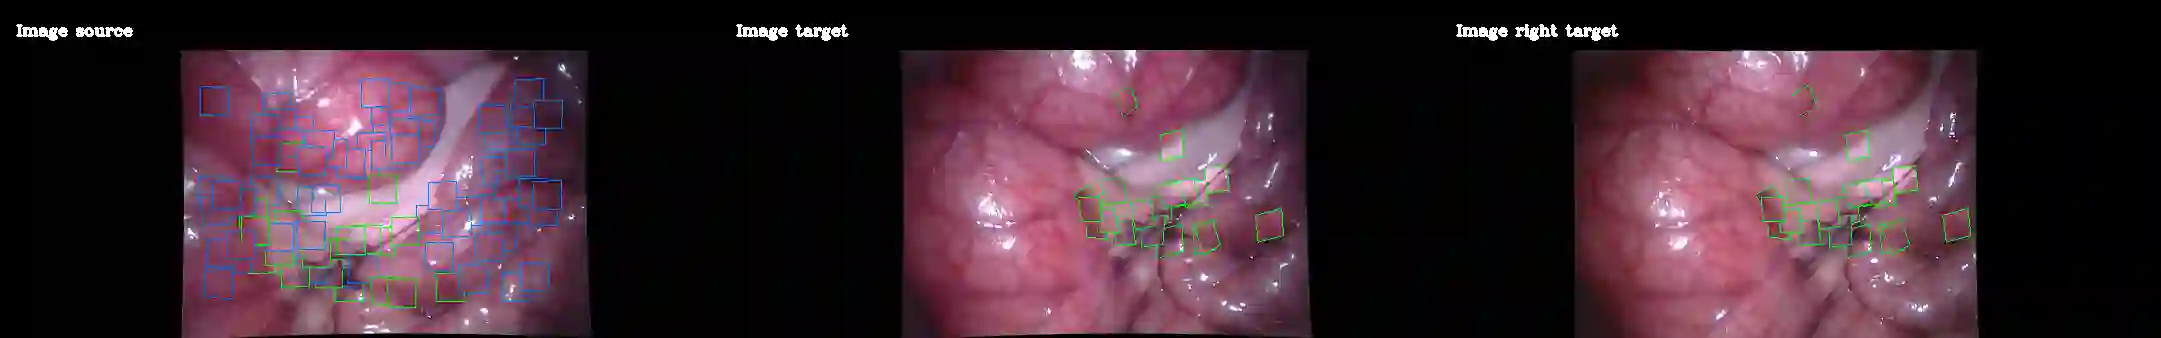

Deformable Monocular SLAM algorithms recover the localization of a camera in an unknown deformable environment. Current approaches use a template-based deformable tracking to recover the camera pose and the deformation of the map. These template-based methods use an underlying global deformation model. In this paper, we introduce a novel deformable camera tracking method with a local deformation model for each point. Each map point is defined as a single textured surfel that moves independently of the other map points. Thanks to a direct photometric error cost function, we can track the position and orientation of the surfel without an explicit global deformation model. In our experiments, we validate the proposed system and observe that our local deformation model estimates more accurately and robustly the targeted deformations of the map in both laboratory-controlled experiments and in-body scenarios undergoing non-isometric deformations, with changing topology or discontinuities.